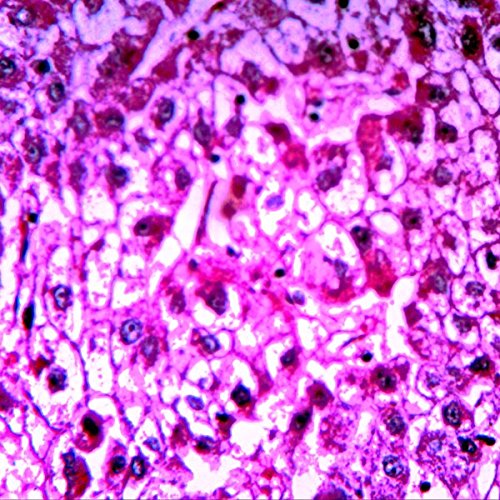

- Set of 12 slides include slides dedicated to human pathology

- The ideal set for high school observation and the human pathology enthusiast